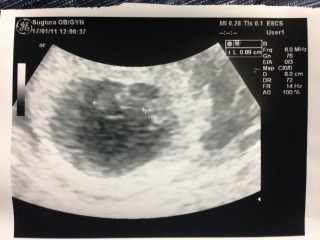

初めての検診から2週間後の2回目の検診。 心配だったけど胎嚢が2センチくらいになり、あかちゃんは0.89センチ。 心臓動いてるのわかりますかー?と先生が言ってるけどわからず。ズームしてもらってやっとピカピカ白黒白黒動いてるのがわかりました。 私の体に命が宿ってるのだなーと実感。卵子から命の誕生の神秘を感じました。 あかちゃんの形はよくわからず、モヤモヤっとしたかたまりでした。 次の検診も2週間後。次は予定日を確定するらしい。